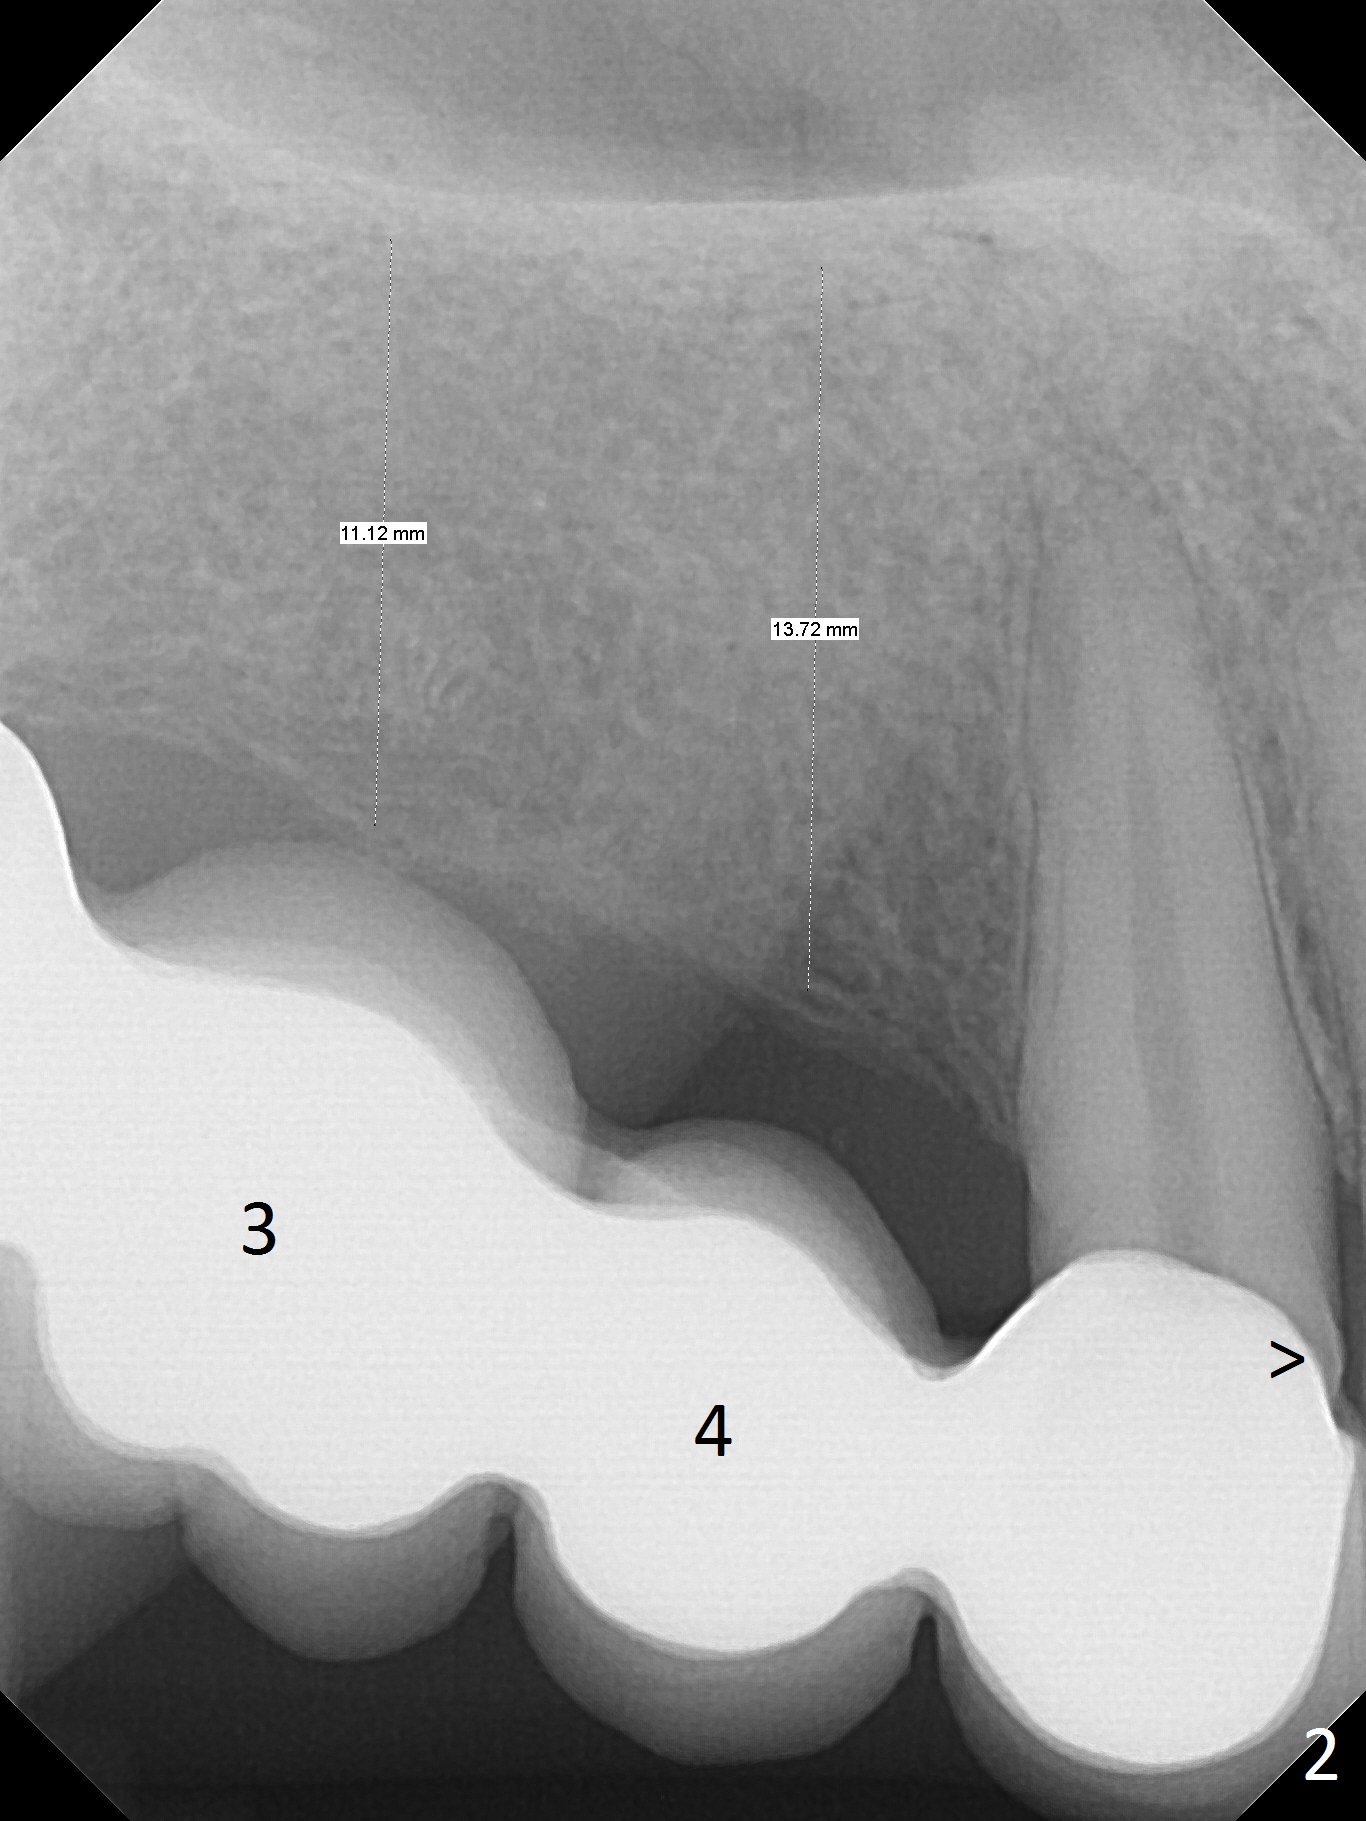

A 39-year-old woman has mobile FPDs at #2-6 (Fig.1,2) and 18-21 (Fig.3,4). Panoramic X-ray (Fig.1,3) was taken 10 years ago, while PAs (Fig.2,4) were taken lately. The abutment at #6 appears to be fractured (Fig.2 >), while that at #18 has 2nd caries (Fig.4 *). Removal of the FPDs determines salvageability of the abutments. The one at #6 may need RCT, B-U and crown or extraction/implant. In any event, implants will be placed at #3, 4, 18 and 20. To avoid the Inferior Alveolar Canal and Mental Loop, the implants will be as lingual as possible (Fig.3,4). For surgical and restorative stents, take Alginate impression as soon as the patient arrives.